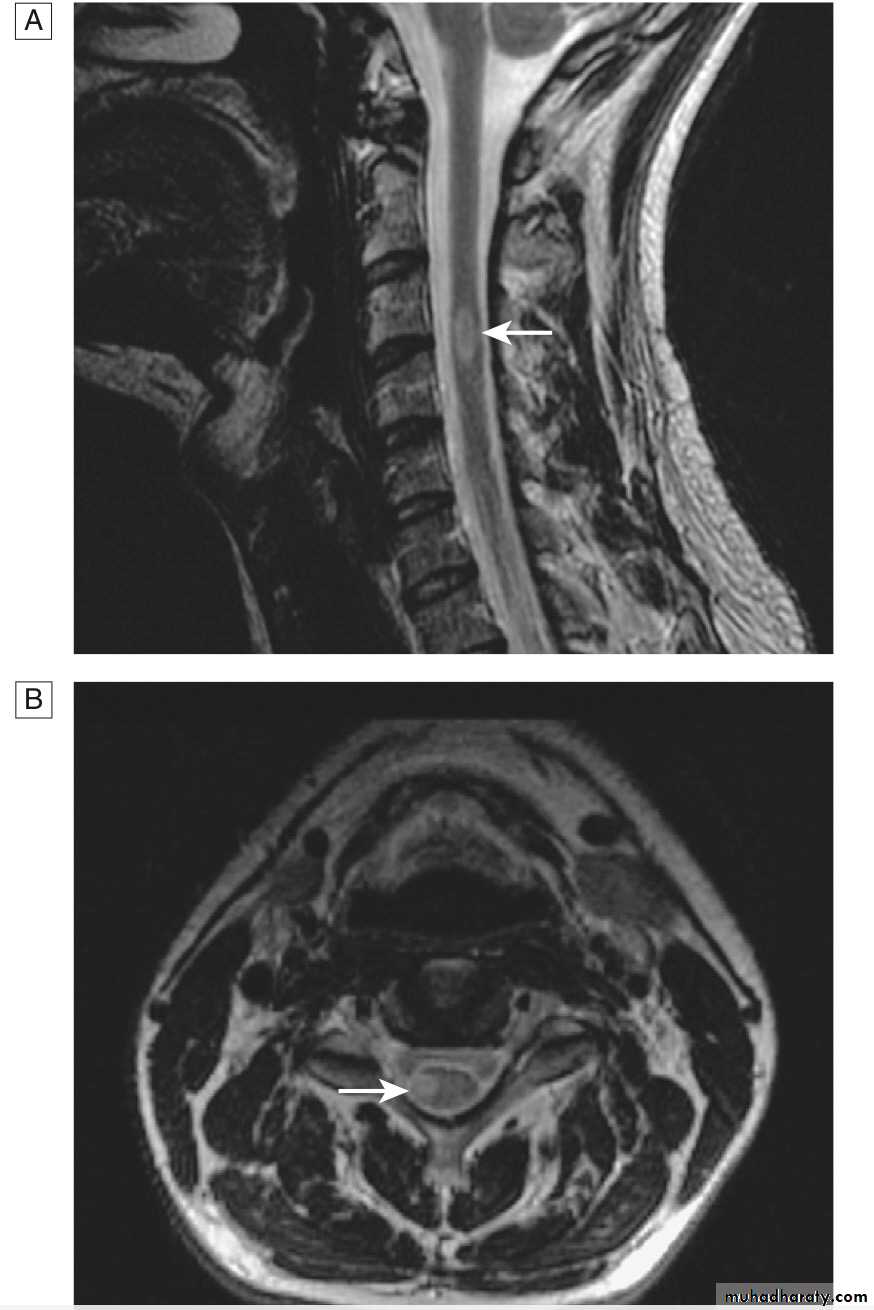

MRI :characteristic abnormalities are found in >95% of patients, although more than 90% of the lesions visualized by MRI are asymptomatic

Lesions are frequently oriented perpendicular to the ventricular surface,(Dawson’s fingers)

Lesions larger than 6 mm located in the corpus callosum, periventricular white matter, brainstem, cerebellum, or spinal cord are particularly helpful diagnostically

myelitis can be severe and transverse (rare in MS) and is typically longitudinally extensive, involving three or more contiguous vertebral segments

A T2-weighted MRI image of her spinal cord shows a lesion extending from T1 to T5 and affecting the central cord. The lesion shows patchy enhancement with gadolinium.

Neuroimaging characteristics are critical for diagnosis. Identification of an intramedullary cord lesion, especially postgadolinium enhancement, is very helpful in a diagnosis of myelitis